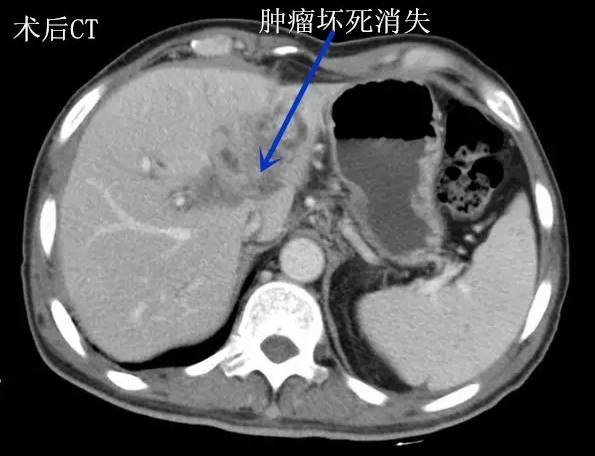

近日,王先生来郑州大学五附院肝胆胰腺外科复诊。黄疸消退,饮食较前明显好转,大小便也恢复正常,体重较前增加5kg。CT显示:肿瘤消失(术后CT图),行T型管造影,胆管通畅(胆管造影图)。王先生说:“手术前,黄人一个;而如今面色红润,能吃能睡,逛街游玩样样行。”

4月8日,经过精心的术前准备,李晓勇教授带领的团队在全麻下行“胆管癌纳米刀术、T型管引流术”,术中明确诊断:肝门部胆管恶性肿瘤。术中超声引导下,李晓勇教授依据电脑程序规划、设计布针路线,精准的将多根电极针分别植入肿瘤组织。电击开始后,1500伏高压脉冲瞬间贯穿病灶,击穿癌细胞。术中在麻醉科胡强夫主任及杨楠护士长带领的医护团队积极配合下,确保了手术成功完成。术后在主管医师张永及宋伟华护士长的精心治疗和护理下,王先生恢复顺利。